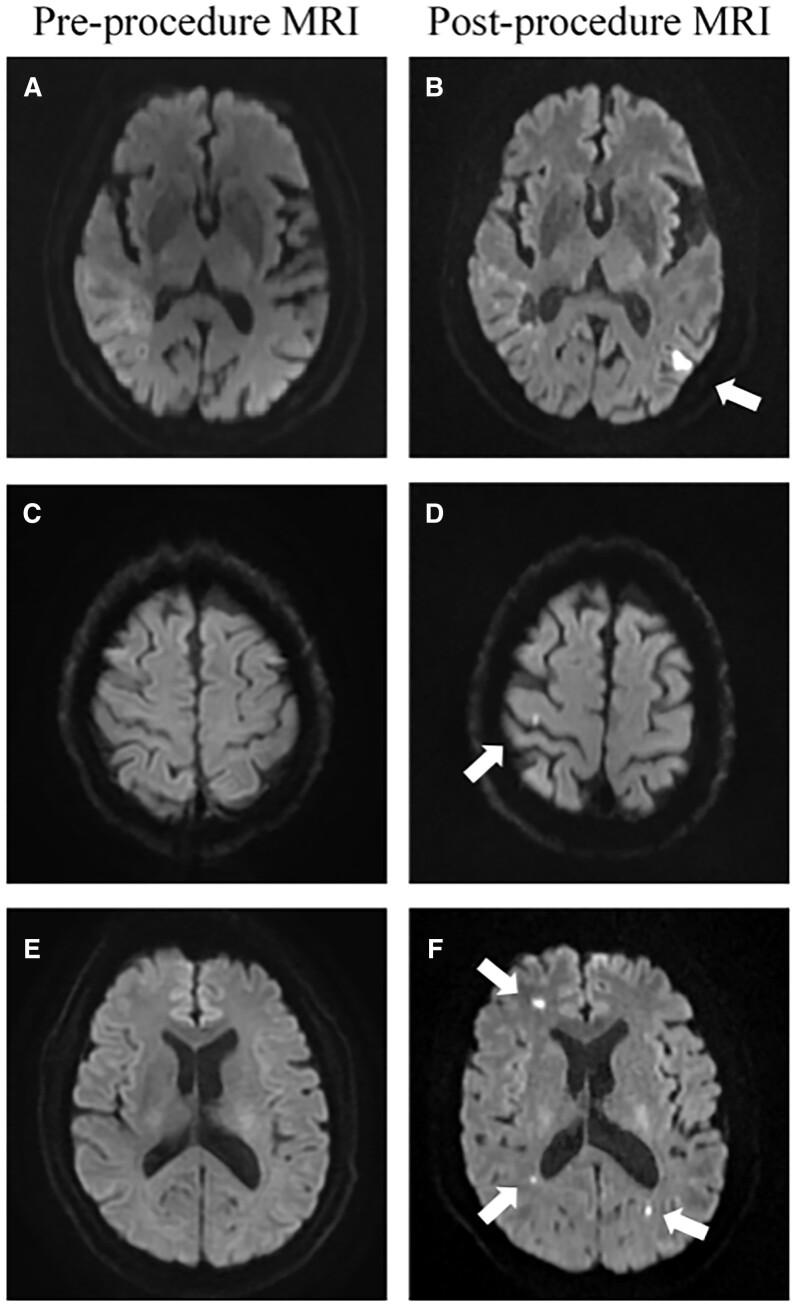

This prospective observational study included consecutive atrial fibrillation patients from 2 independent cohorts (left atrial appendage excision (LAAE) cohort and left atrial appendage occlusion cohort) between September 2018 and December 2020. All patients underwent cerebral magnetic resonance imaging before and after the procedure. Silent cerebral embolism was defined as new focal hyperintense lesions detected only on postprocedural sequence.

Thirty-two patients from the LAAE cohort and 42 patients from the occlusion cohort were enrolled. A significantly lower incidence of silent cerebral embolism was observed in the LAAE cohort as compared with occlusion (6.3% vs 54.8%, P < 0.001). In the left atrial appendage occlusion cohort, patients who developed silent cerebral embolism after the procedure had significantly higher CHA2DS2-VASc scores [odds ratio (OR) 2.172; 95% confidence interval (CI) 1.149-4.104; P = 0.017], longer occlusion placement time (OR 1.067; 95% CI 1.018-1.118; P = 0.006) and lower peak activated clotting time level after transseptal puncture (OR 0.976; 95% CI 0.954-0.998; P = 0.035).